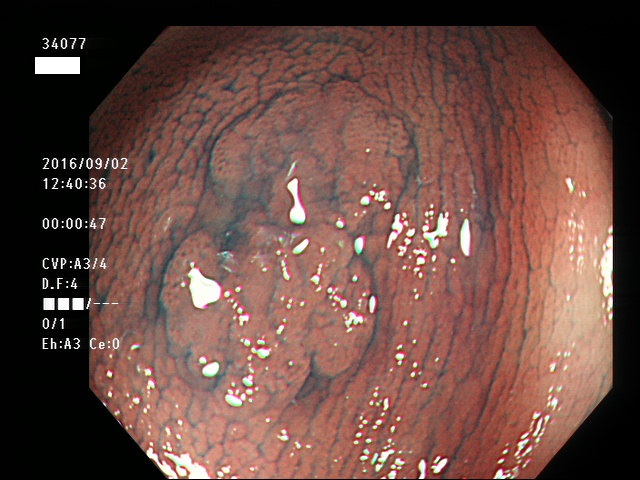

上記100名より抽出した平坦・陥凹型腺腫(=癌化の危険が高いが見落としやすい病変)の内視鏡写真